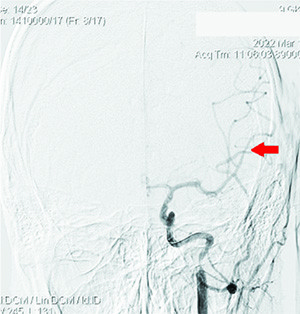

Рисунок 2. Окклюзия ВСА слева, коллатеральное заполнение сосудов левой гемисферы из правой ВСА и позвоночных артерий.Спустя 40 минут после начала тромболизисной терапии пациентка доставлена в ангиографический кабинет для проведения рентгенэндоваскулярного вмешательства.

Рисунок 3. Локальная окклюзия ветвей первого порядка левой СМА после бифуркации.В 12:15 под местной анестезией выполнена пункция передней стенки правой бедренной артерии.

Проведена диагностика: определялась окклюзия несколько дистальнее устья ВСА слева, коллатеральное заполнение сосудов левой гемисферы из правой ВСА и позвоночных артерий, локальная окклюзия ветвей первого порядка левой СМА после бифуркации (см. рис. 2 и 3).